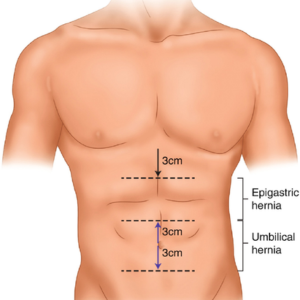

Umblical Hernia

Epigastric Hernia